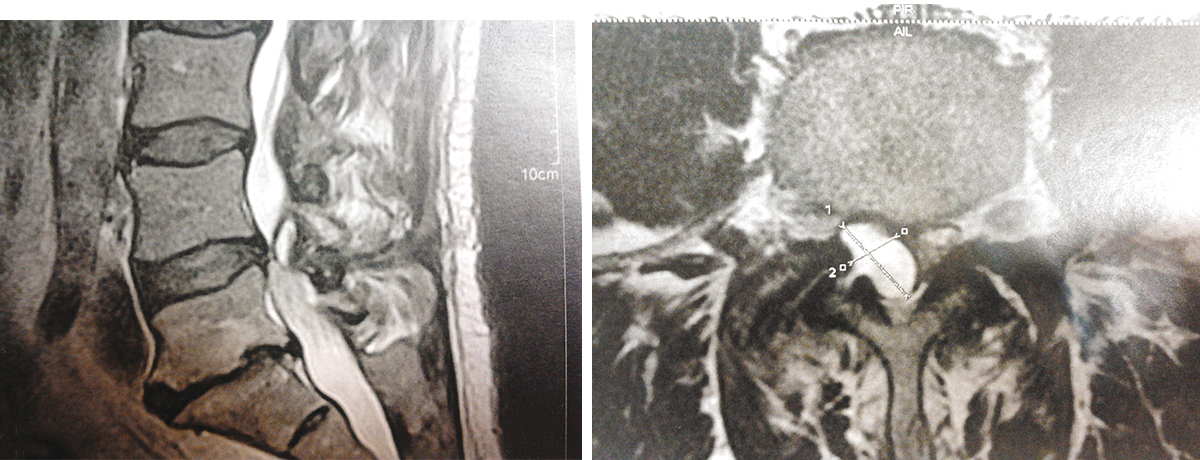

Quel est votre diagnostic ?

Il s’agit d’un très gros kyste articulaire postérieur responsable d'une sciatique L5 droite vu sur une IRM (T2, coupe sagittale et axiale). La racine nerveuse L5 peut être comprimée par un massif articulaire arthrosique, mais parfois par un kyste synovial qui se développe à ce niveau. Les kystes développés en regard des articulaires postérieures du rachis lombaire se manifestent le plus souvent par une lomboradiculalgie : sciatique ou cruralgie. On distingue deux types de kystes : les kystes synoviaux ou synovialomes : leur paroi (plus ou moins épaisse, fibreuse, parfois calcifiée) est tapissée de tissu synovial, hyperplasique. Le contenu est fait d’une substance mucoïde, brunâtre ou jaunâtre ; les kystes nodulaires sans synoviale : ils contiennent un matériel amorphe, gélatineux, pouvant se calcifier, dans lequel il y a parfois des dépôts d’hémosidérine. Les deux variétés de kystes ont les mêmes circonstances étiologiques et les mêmes conséquences cliniques. Les kystes symptomatiques sont rares : ils ne représentent que 1 % des sciatiques non discales. Dans la grande majorité des lomboradiculalgies des membres inférieurs, la cause est d’origine discale (hernie discale) et/ou arthrosique. L’interrogatoire et l’examen clinique sont les étapes clés du diagnostic, permettant également de rechercher des signes de gravité et d’écarter les diagnostics différentiels. Les progrès de l’imagerie, et notamment de l’IRM, ont considérablement simplifié la démarche diagnostique, sous réserve de confronter avec une objectivité rigoureuse les images aux données cliniques. Ainsi, la conduite diagnostique doit permettre de répondre à deux questions : la douleur correspond-elle à une lomboradiculalgie commune (discale et/ou arthrosique) ou est-elle symptomatique d’une autre cause (tumorale par exemple) ? En cas de lomboradiculalgie commune, s’agit-il d’une hernie discale, d’une arthrose, d’un canal lombaire rétréci ?